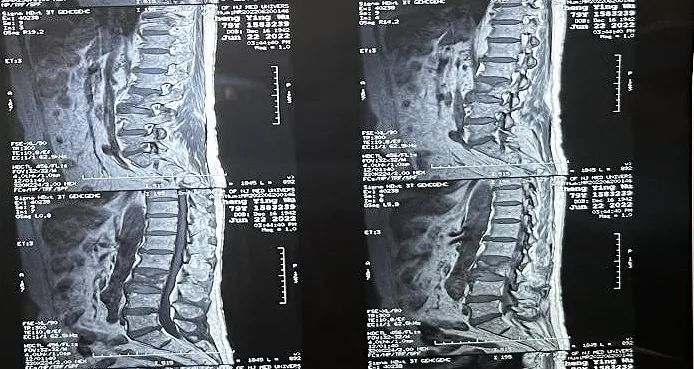

患者情況:腰椎L3壓縮性骨折

南京醫(yī)科大學(xué)第二附屬醫(yī)院骨科副主任醫(yī)師王伯堯帶領(lǐng)團(tuán)隊(duì)成功完成經(jīng)皮椎體球囊擴(kuò)張成形術(shù)(PKP)。該患者為腰椎陳舊性壓縮性骨折,腰部疼痛難忍,活動受限,生活受到影響。王醫(yī)生借助普愛醫(yī)療大平板C臂機(jī)高清的圖像及靈活的擺位,快速定位椎弓根位置,確定進(jìn)針點(diǎn),使得手術(shù)得以更加高效和準(zhǔn)確地完成。

患者術(shù)前影像